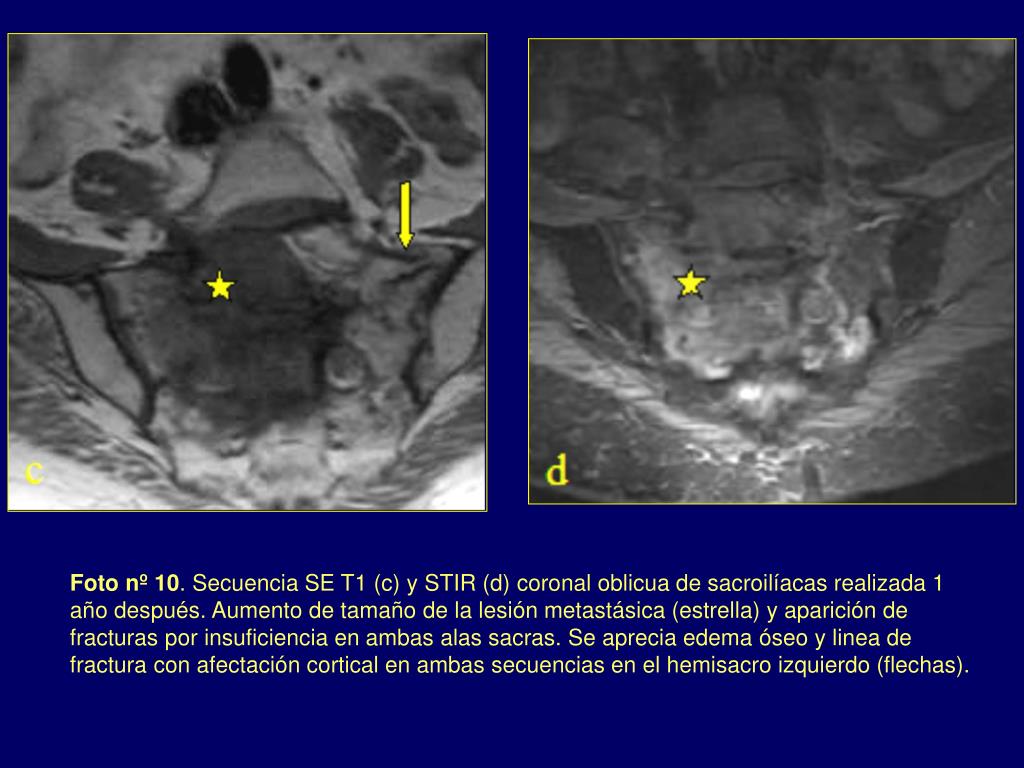

12. Foto nº 10. Secuencia SE T1 (c) y STIR (d) coronal oblicua de sacroilíacas realizada 1 año después. Aumento de tamaño de la lesión metastásica (estrella) y aparición de fracturas por insuficiencia en ambas alas sacras. Se aprecia edema óseo y linea de fractura con afectación cortical en ambas secuencias en el hemisacro izquierdo (flechas).